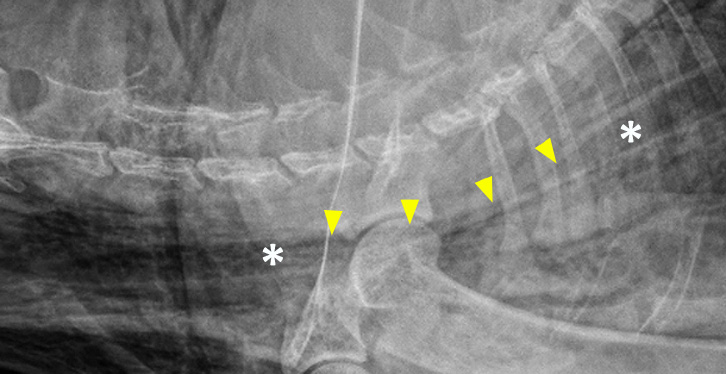

Latérale du cou